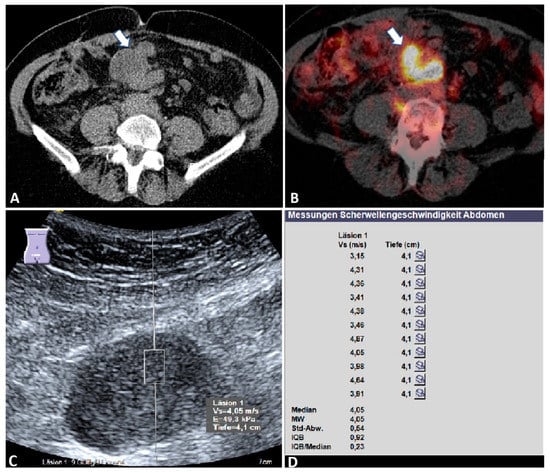

3.2. B-Mode Ultrasound Data

3.3. Acoustic Radiation Force Impulse Examinations